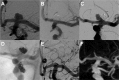

Figure 1

Unruptured aneurysm of the left internal carotid artery (ICA) terminus (A), treated by coiling (B). About 14 years later, a large recurrence (C) was treated using a WEB SL (D). Control DSA (E) including 3D DSA (F with metal subtraction) after 11 months confirms complete occlusion. Note a second aneurysm of the intracranial ICA with stable occlusion after the initial endovascular treatment.